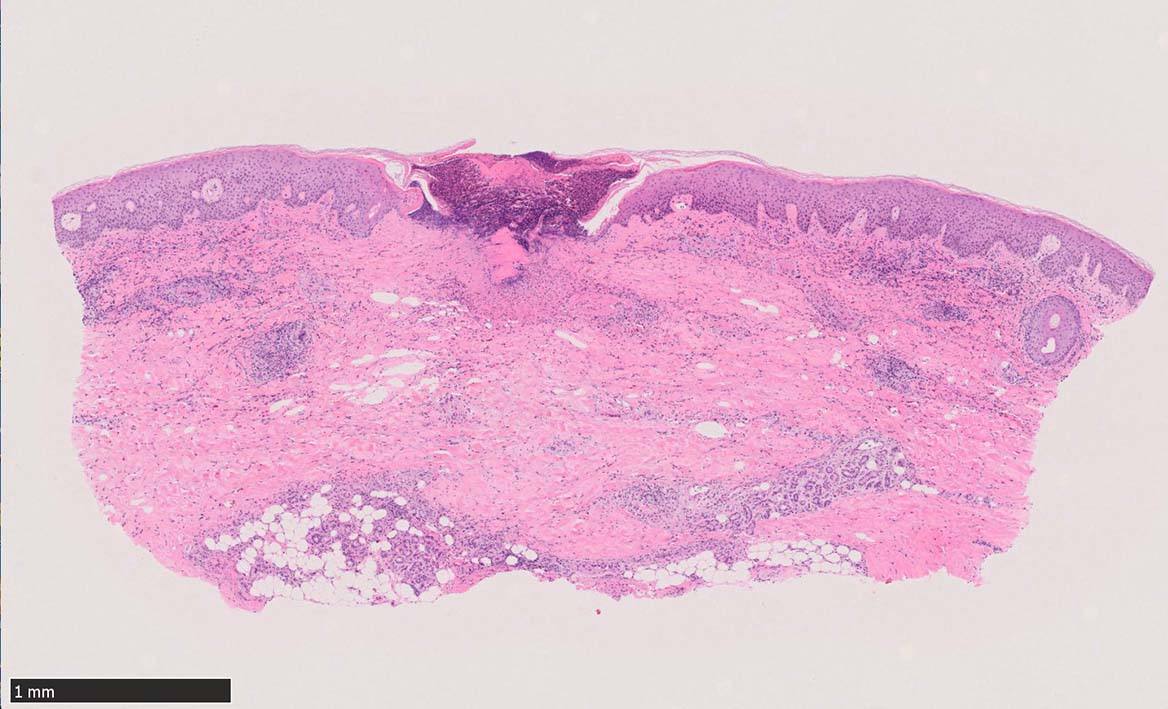

IWT-case02 1歳9ヶ月男児 項部の血豆様腫瘤に気づき来院.

マダニ科マダニ(4属)では触肢と口器は短くなっており,そのために, 吸血後24時間程度経過すると,唾液腺で産生されるセメント様物質を分泌して口下片全体を包みこみ,体を宿主にしっかりと固定する.

(case02の皮膚表面にみられる硝子様の層がそれに相当するようです。)

特に体部をつぶすとマダニ体内の病原体が血液とともに人間体内に逆流し感染リスクを高めるおそれがある. 虫体を無理に除去して口下片が遺残すると掻痒性結節が数ヶ月続くこともある.また膿瘍, 肉芽腫, アレルギー反応の原因になることがある。